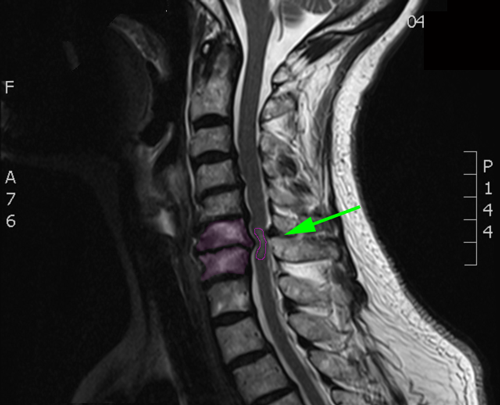

Διάγνωση Απαραίτητες είναι: Η λεπτομερής λήψη ιστορικού και η κλινική εξέταση, Η μαγνητική τομογραφία της αυχενικής μοίρας της σπονδυλικής στήλης, Σε ορισμένες περιπτώσεις: Οι ακτινογραφίες της αυχενικής μοίρας της σπονδυλικής στήλης, και ενίοτε οι δυναμικές λήψεις σε κάμψη και έκταση, Ο νευροφυσιολογικός έλεγχος με ηλεκτρομυογράφημα και ταχύτητα αγωγής νεύρων άνω ή 4 άκρων ή/και σωματοαισθητικά προκλητά δυναμικά, |

Η αξονική τομογραφία της αυχενικής μοίρας της σπονδυλικής στήλης με τρισδιάστατη ανασύνθεση.